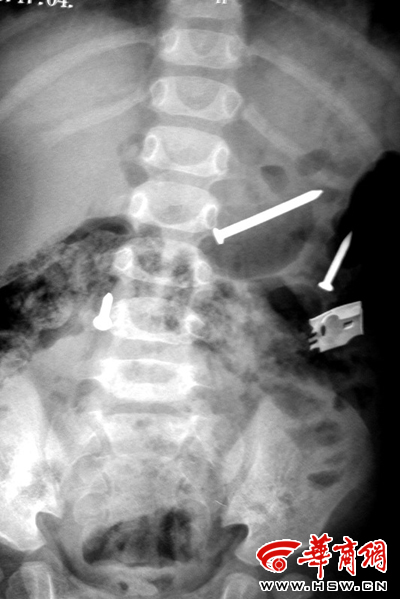

排出铁钉之后复检拍片又显示肚内有铁钉(刘立春摄)

来自榆林市米脂县的这名一岁半女孩,在最近一个多月内,从体内不断排出铁钉,共达20多枚。更为奇怪的是,在医院拍片显示体内已没有铁钉时,过几天铁钉还会出现。